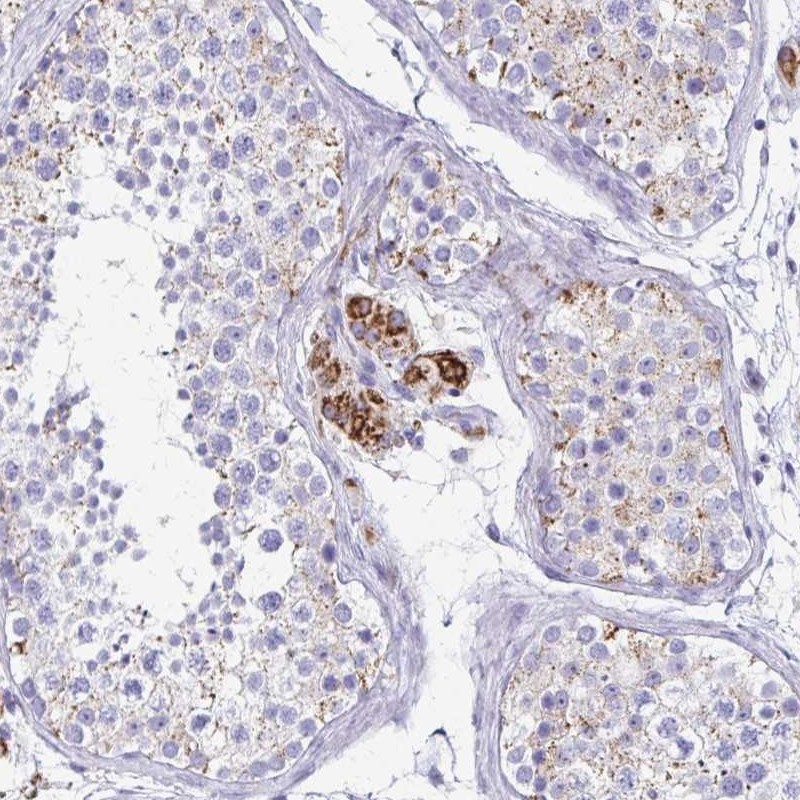

Immunohistochemical staining of human testis shows strong cytoplasmic positivity in Leydig cells.